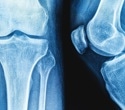

Bone mineral density test. Women over 65, anyone who has a fracture after age 50, and others with significant risk factors should get a bone density test. Bone density tests use xrays or sound waves to measure the strength of the bones. Bone density tests are safe, painless, and quick, and indicate the health of bones. Check with your health care professional about your risks and find out if you need a bone density test.